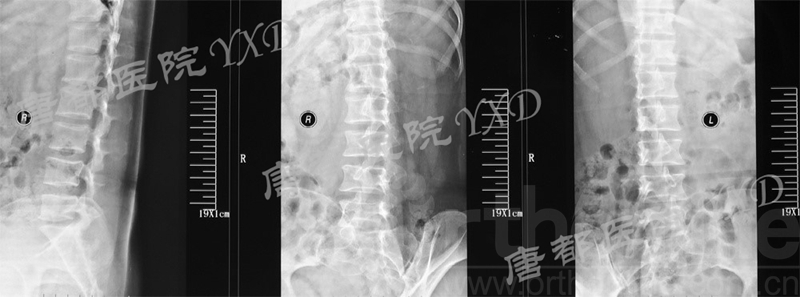

影像学检查:

诊断:腰椎间盘突出症术后复发

手术方案:显微镜辅助MI-TLIF腰椎翻修术